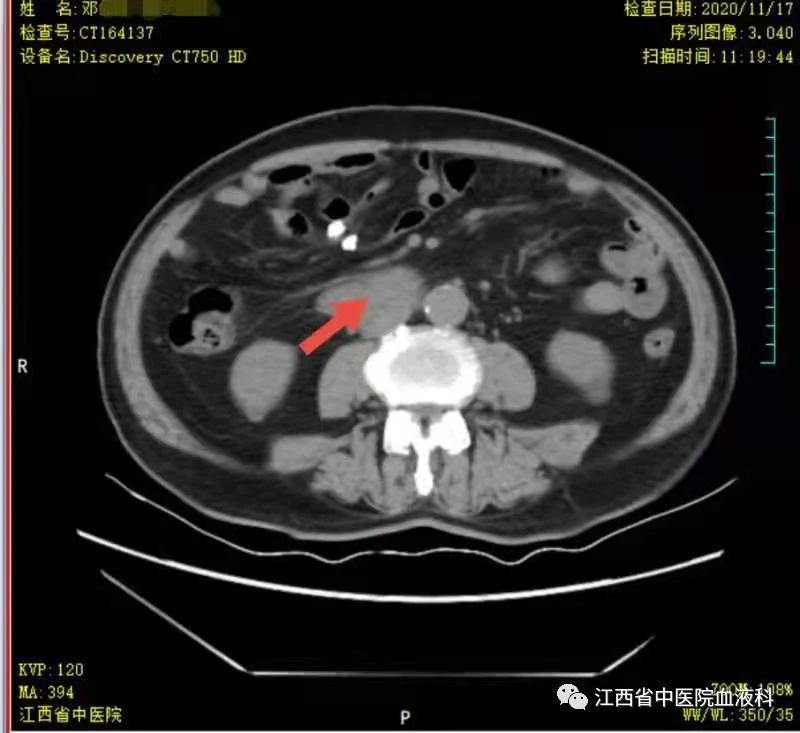

2020年10月中旬邓大爷在家人的陪同下来我科就诊,全腹部增强CT提示:右侧睾丸切除术后复查:1.腹膜后(胰头后下方)、双侧肾上腺区团块状异常强化影。2.肝左内叶上段小囊肿,双肾小囊肿,较前相仿。3.右侧腹股沟前方、皮下条索、小片影,境界不清,较前减小,拟为术后改变。4.右下腹腔少许钙化淋巴结,较前相仿。因病情危急,考虑邓大爷高龄、体能差、窦性心动过缓(平均心率50次/分)心脏功能差等情况,经讨论于2020-10-24起第一次行减剂量方案R-miniCHOP(利妥昔单抗700mg d0、环磷酰胺700mg d1、多柔比星40mg d1、长春瑞滨20mg d1、地塞米松10mg d1-5)方案。第一次化疗后评估病情,腹腔瘤体缩小了2/3,取得了很好的治疗效果,可邓大爷心脏却亮起了红灯,经过了积极护心等支持治疗后,大爷心脏功能有所恢复。遂于2020-11-19、2020-12-10行2次R-miniCOP方案(去除了具有心脏毒性的多柔比星),三次化疗结束后予评估病情,提示腹腔包块明显缩小,淋巴瘤病情有所好转。